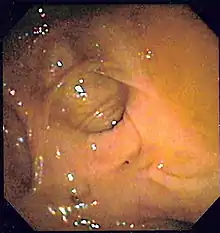

| A positive fecal occult blood test | |